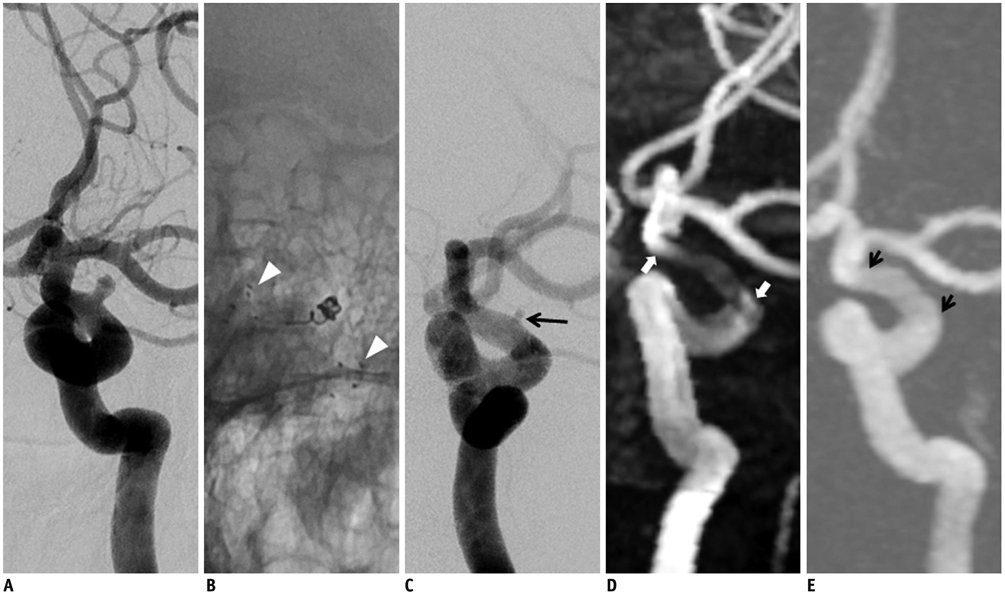

To evaluate the usefulness of time-resolved contrast enhanced magnetic resonance angiography (4D MRA) after stent-assisted coil embolization by comparing it with time of flight (TOF)-MRA.

TOF-MRA and 4D MRA were obtained by 3T MRI in 26 patients treated with stent-assisted coil embolization (Enterprise:Neuroform = 7:19). The qualities of the MRA were rated on a graded scale of 0 to 4. We classified completeness of endovascular treatment into three categories. The degree of quality of visualization of the stented artery was compared between TOF and 4D MRA by the Wilcoxon signed rank test. We used the Mann-Whitney U test for comparing the quality of the visualization of the stented artery according to the stent type in each MRA method.

RESULTS

The quality in terms of the visualization of the stented arteries in 4D MRA was significantly superior to that in 3D TOF-MRA, regardless of type of the stent (p < 0.001). The quality of the arteries which were stented with Neuroform was superior to that of the arteries stented with Enterprise in 3D TOF (p < 0.001) and 4D MRA (p = 0.008), respectively.

4D MRA provides a higher quality view of the stented parent arteries when compared with TOF.